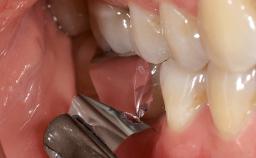

Despite anti-infective surgical treatment, some patients may experience recurrent infection and progressive bone loss requiring additional treatment. This case describes a conservative approach using an implant retrieval tool without the need for excessive bone removal or use of a trephine.

A 65-year-old female patient was referred to the periodontist for assessment and management of infection associated with an implant at site 12. The general dentist had noted suppuration on probing during examination.